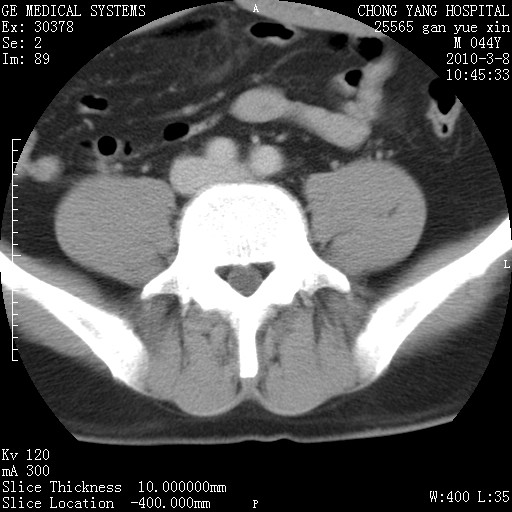

标题: CT24940:主动脉增强,典型病例。 [打印本页]

标题: CT24940:主动脉增强,典型病例。

夹层动脉瘤。

动脉夹层

夹层动脉瘤,典型

主动脉夹层。

动脉夹层的分型:

⒈debakey分型:根据主动脉夹层累及部位,分为三型:ⅰ型:原发破口位于升主动脉或主动脉弓部,夹层累及升主动脉、主动脉弓部、胸主动脉、腹主动脉大部或全部,少数可累及髂动脉。ⅱ型:原发破口位于升主动脉,夹层累及升主动脉,少数可累及部分主动脉弓。ⅲ型:原发破口位于左锁骨下动脉开口远端,根据夹层累及范围又分为ⅲa,ⅲb。ⅲa型:夹层累及胸主动脉。ⅲb型:夹层累及升主动脉、腹主动脉大部或全部。少数可累及髂动脉。

⒉stanford分型:a型:夹层累及升主动脉,无论远端范围如何。b型:夹层累及左锁骨下动脉开口以远的降主动脉。

夹层动脉瘤,少量胸水

夹层动脉瘤;左侧少量胸腔积液。

典型主动脉夹层。